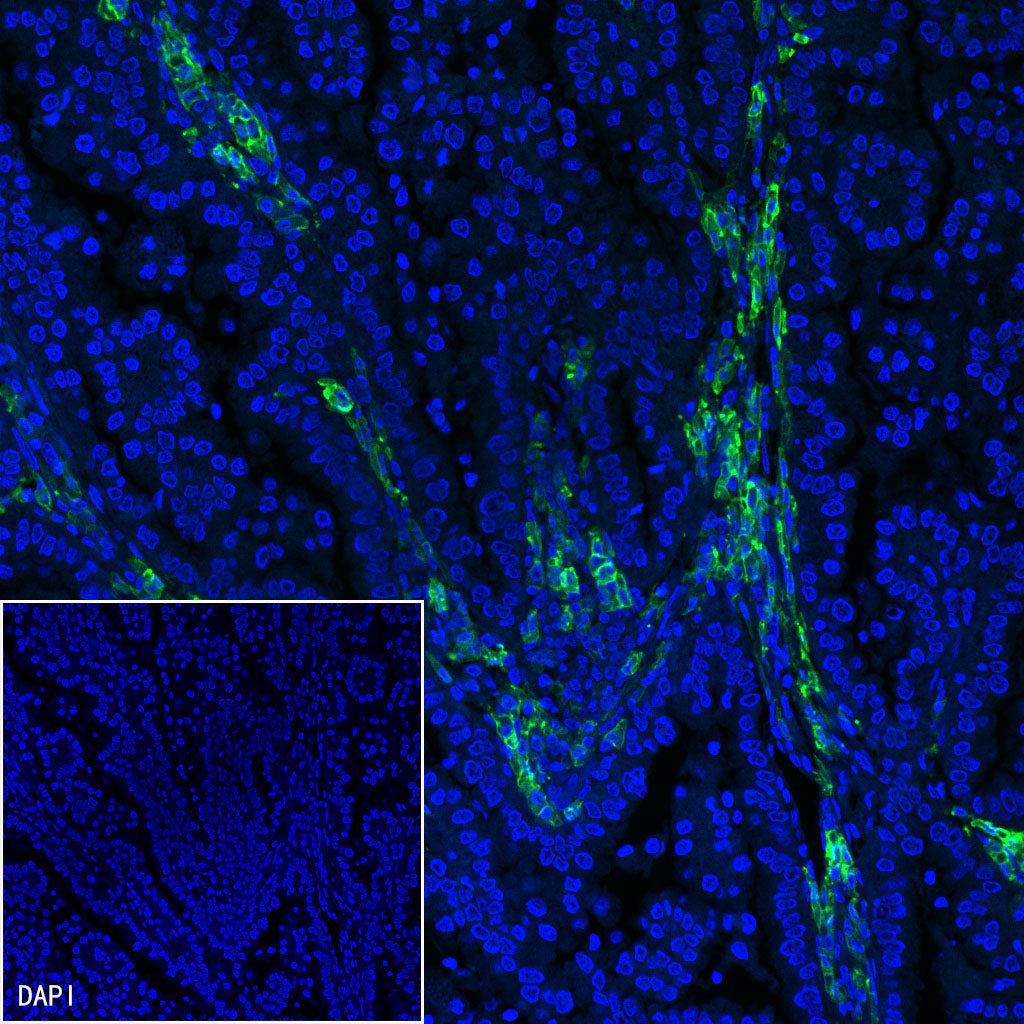

Immunofluorescence

IF shows positive staining in paraffin-embedded human colon cancer. Anti-CD38 antibody was used at 1/500 dilution (Green) and incubated overnight at 4°C. Goat polyclonal Antibody to Mouse IgG - H&L (Alexa Fluor® 488) (S0B4017) was used as secondary antibody at 1/500 dilution. Counterstained with DAPI (Blue). Heat mediated antigen retrieval with EDTA buffer pH9.0 was performed before commencing with IF staining protocol.